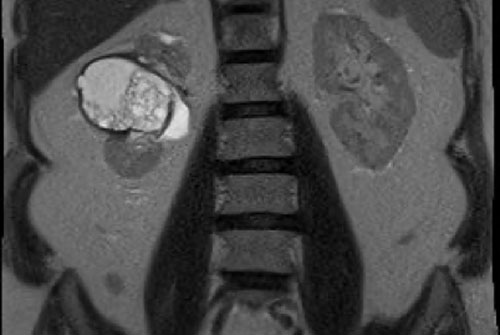

Hình chụp CT thì tĩnh mạch cửa cho thấy một tổn thương dạng nang không đồng nhất ở thận trái.

Vùng tăng tỷ trọng có ngấm thuốc trên ảnh chuỗi xung T1W có ức chế mỡ, phù hợp với một nốt đặc trong nang Bosniak 4.